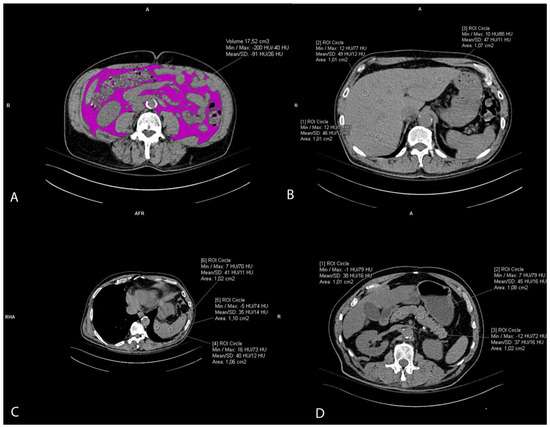

2.3. Visceral Fat Volume Measurement

The visceral fat volume, expressed in cm3, was measured on the native/pre-contrast CT scans of the abdomen and pelvis semiautomatically. First, at the umbilical level, a line at the inner contour of the abdominal muscles was carefully manually drawn. The Hounsfield unit of fat tissue attenuation from −200 and −40 HU was automatically segmented within this area surrounded by the manually drawn line. Finally, the visceral fat volume was automatically calculated by the Siemens syngo.via VB60A_HF08 software (Figure 2A). The intraclass correlation coefficient (ICC) was 0.982 (95% CI 0.96–0.99).

Figure 2. Representative axial CT images showing visceral fat volume estimation (A), liver attenuation measurement (B), spleen attenuation measurement (C), and pancreas attenuation measurement (D).

2.4. Ectopic Fat Accumulation Measurements

Liver attenuation was measured by drawing three round regions of interest (ROI) of the approximately same size, 1 cm2, at the portal vein level representing HU. The ROI was placed within the left lobe, right anterior lobe, and right posterior lobe of the liver. All ROIs were carefully distributed in the liver parenchyma, excluding the biliary, vascular, and other structures. (Figure 2B). The used liver attenuation was an average of the three HU at the mentioned measurement sites. Spleen attenuation was very similarly measured by averaging three manually placed round ROIs (approximately 1 cm2), representing HU, at three different areas of spleen on the same slice (Figure 2C). After the liver and spleen attenuation measurements, the liver-to-spleen attenuation ratio was calculated by dividing the average liver with average spleen attenuation. The index was used as a measure of ectopic fat accumulation in the liver parenchyma (liver steatosis). Pancreas attenuation measurement was similarly performed using ROI at the pancreatic parenchyma at the uncinate process, and the head, neck, body, and tail of the pancreas (Figure 2D). An average of the HU in the pancreas was calculated, and then the pancreas-to-spleen attenuation ratio was calculated in the same manner, by dividing the mean attenuation values of the pancreas and spleen. The pancreas-to-spleen attenuation was used as a measure of ectopic pancreatic fat accumulation (pancreatic steatosis). The ICC for the liver-to-spleen ratio was 0.939 (95% CI 0.80–0.97), and for the pancreas-to-spleen ratio it was 0.852 (95% CI 0.71–0.93).